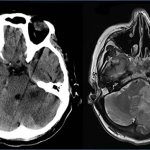

Рисунок 6. Очаги поражения центральной нервной системы при рассеянном склерозе на МРТ выглядят как белые бляшки.

Рисунок 7. В зависимости от места поражения нервной системы при рассеянном склерозе может быть разная симптоматика: от тремора и атаксии при повреждении мозжечка до эмоциональных расстройств при локализации очагов в лобных долях.